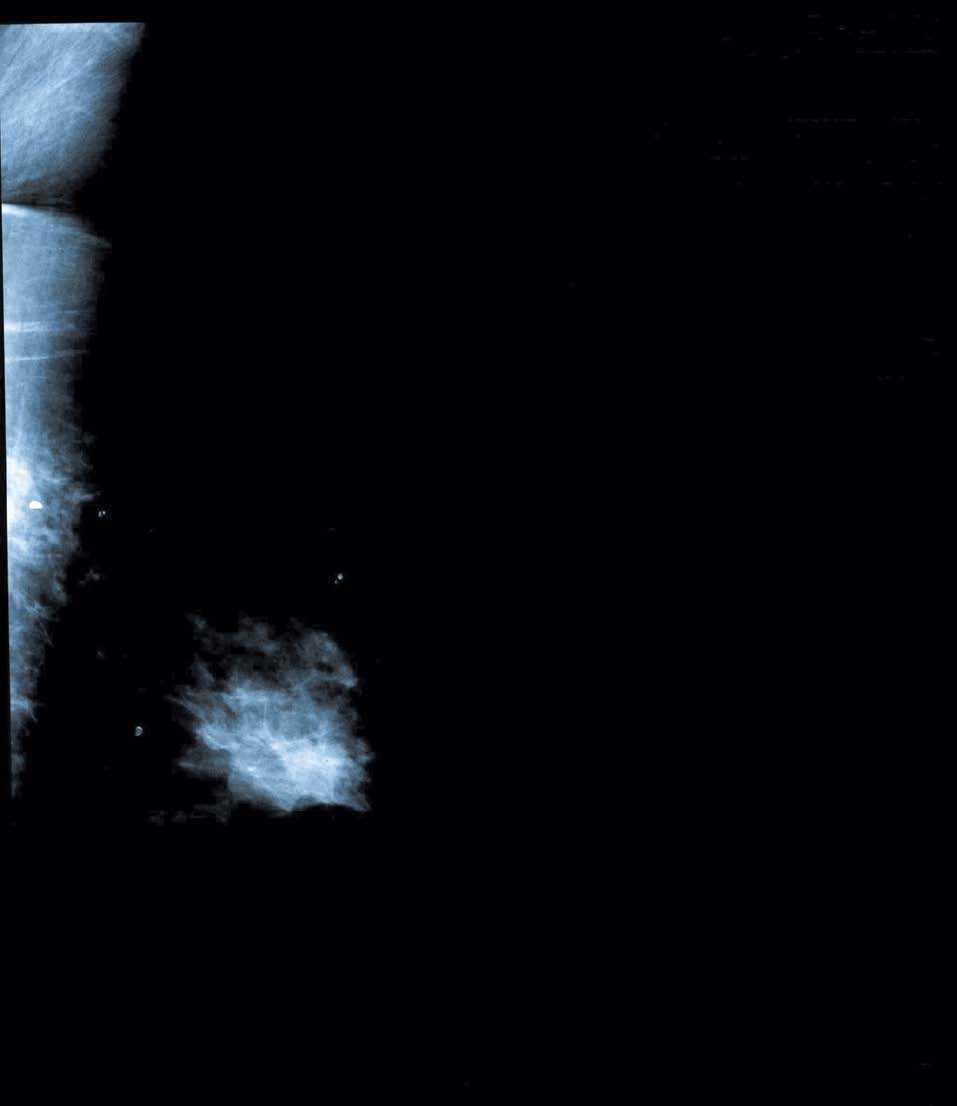

En una mamografía realizada en agosto de 2004 se visualizaban 3 nódulos en la mama derecha, uno de ellos en la región retroareolar y los otros 2 en el cuadrante superoexterno; uno de los nódulos localizado en el cuadrante superoexterno presenta un contorno parcialmente mal definido de la cara posterior en la proyección craneocaudal (figs. 3 y 4).

Figura 3. Mamografía derecha. Nodulos retroalveolar y en cuadrante superoexterno.

Figura 4. Mamografía derecha. Nodulos retroalveolar y en cuadrante superoexterno.

Ante estos hallazgos, y dados los antecedentes clínicos de la paciente, se realizó una PAAF de dichos nódulos, que informó de metástasis de melanoma.